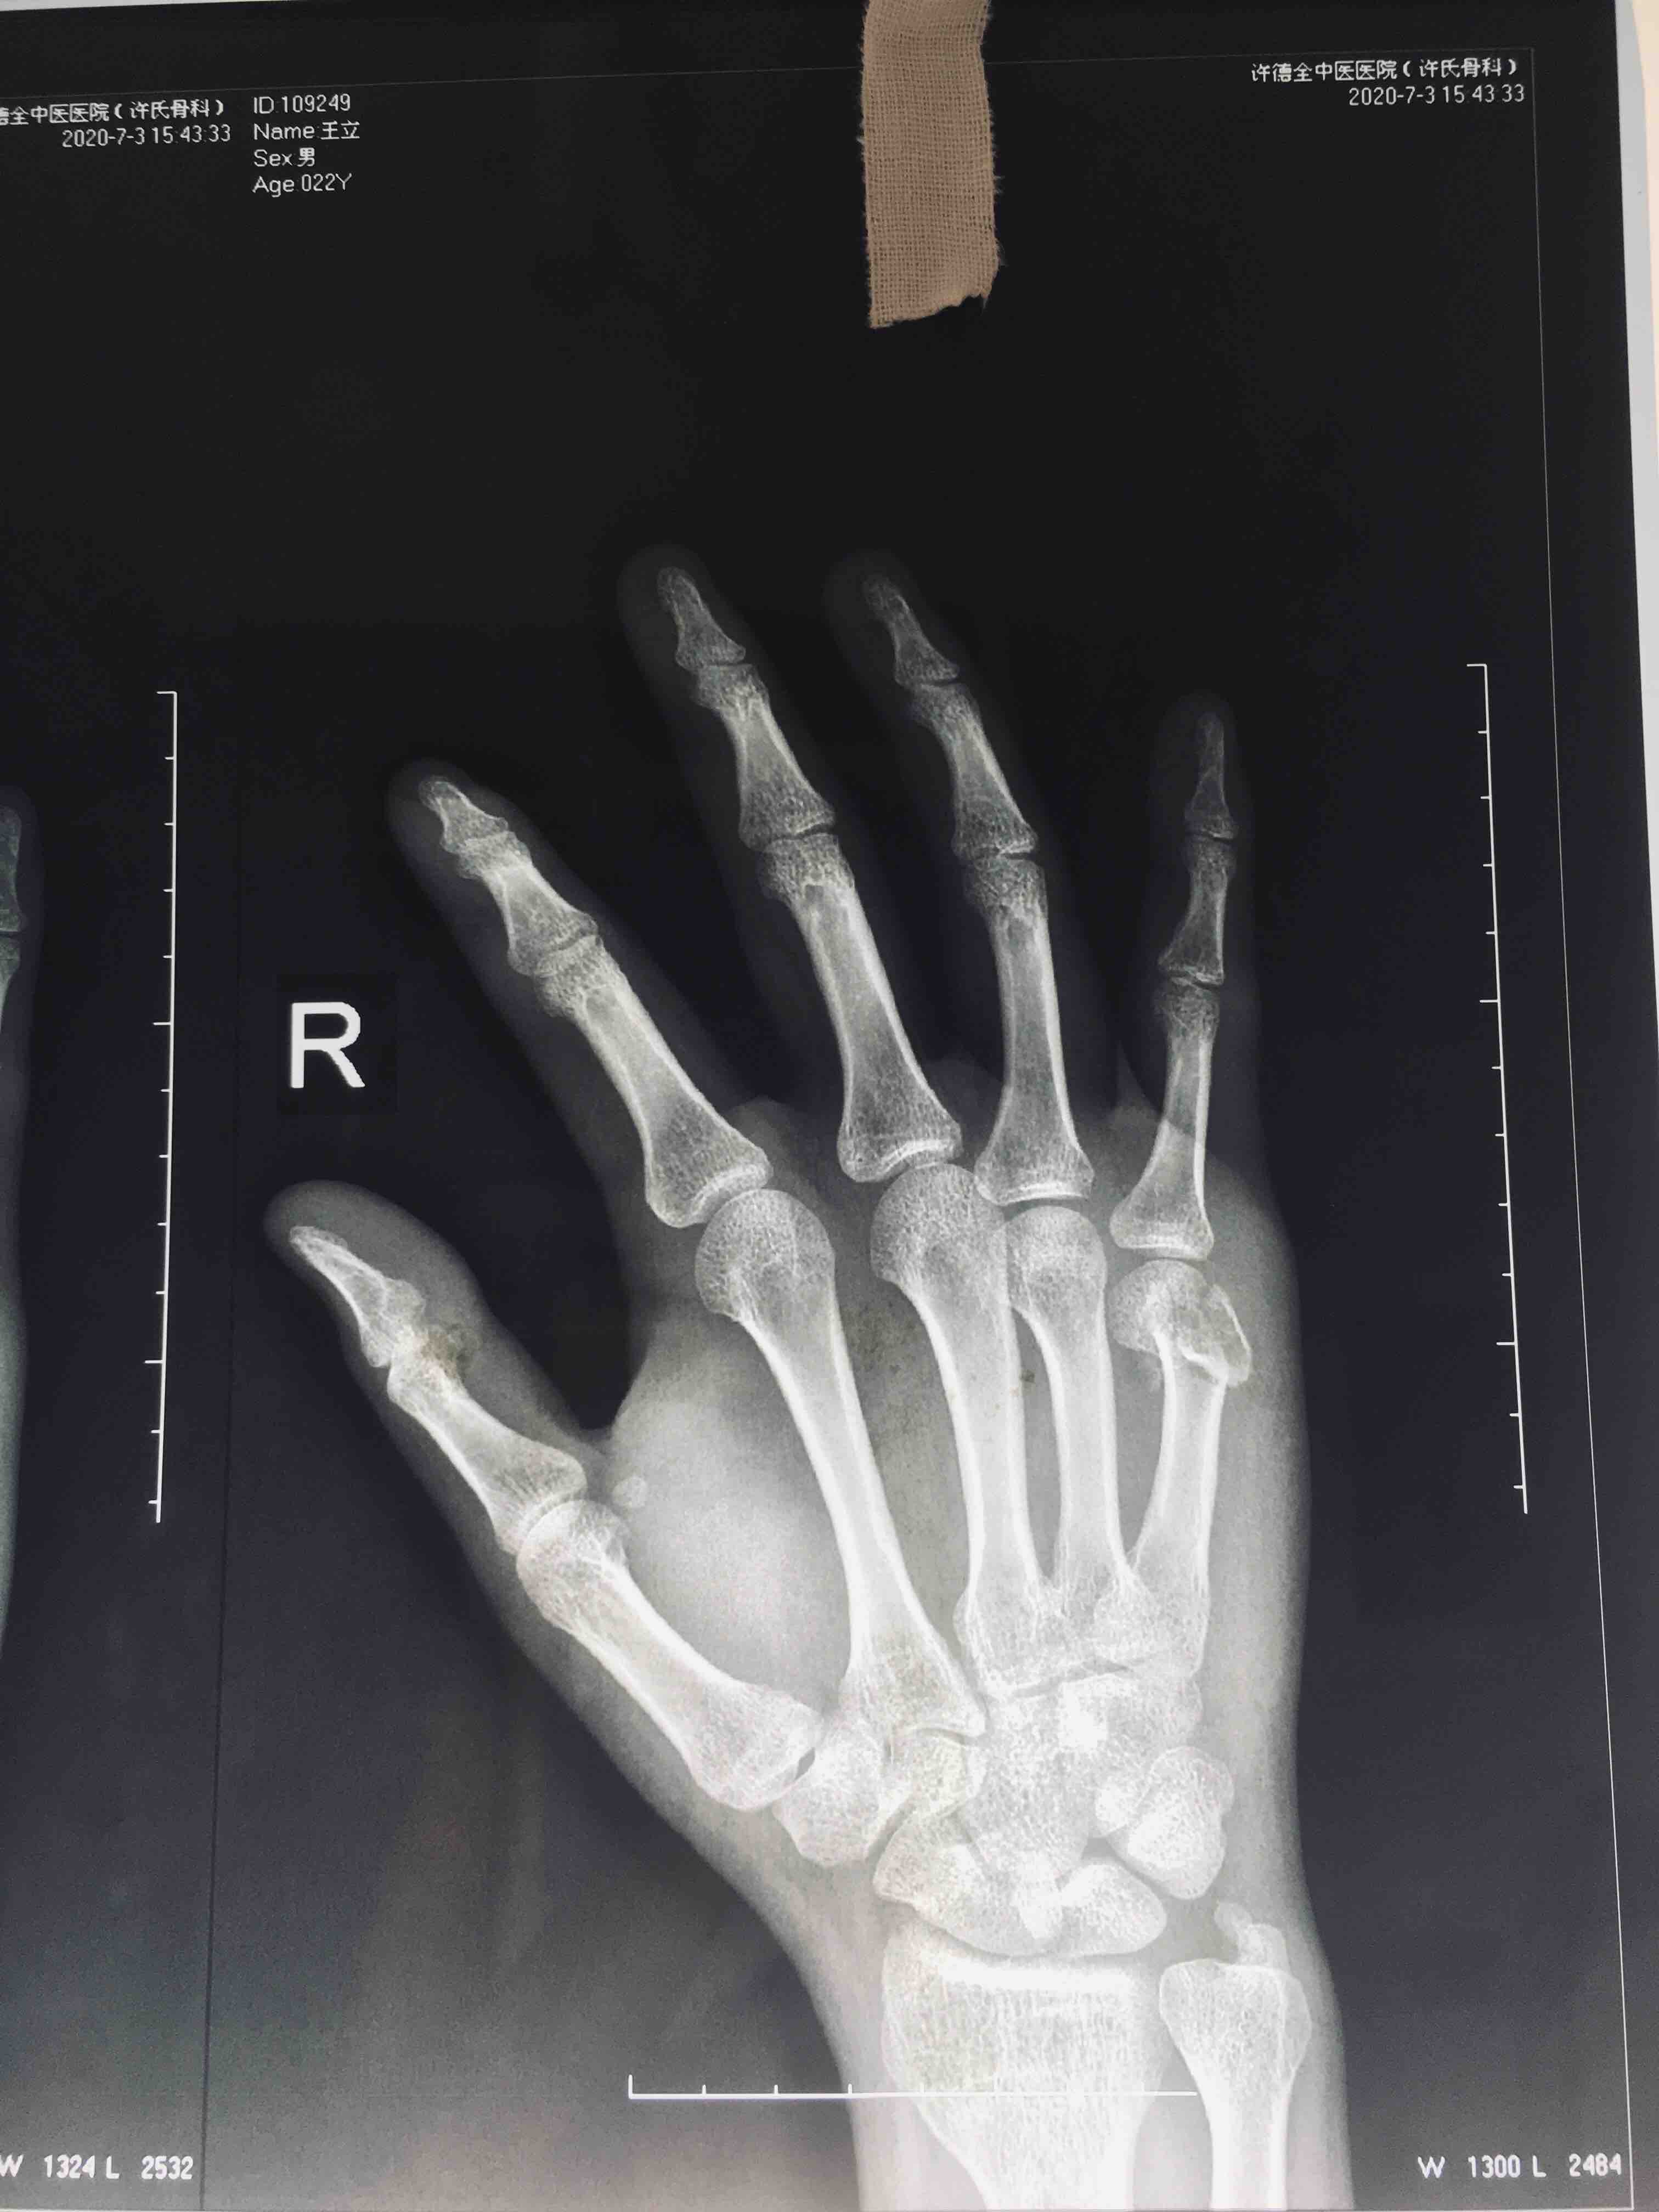

掌骨头粉碎性骨折(切复内固定术)

摔伤后右手疼痛1小时入院。既往因右手第五掌骨头骨折行闭合复位固定术。

右手第五掌指关节处肿胀,局部皮色皮温正常,压痛及纵向叩击痛阳性,末梢血运感觉正常,掌指关节活动受限。

臂丛麻醉下行切复内固定术,术后制动